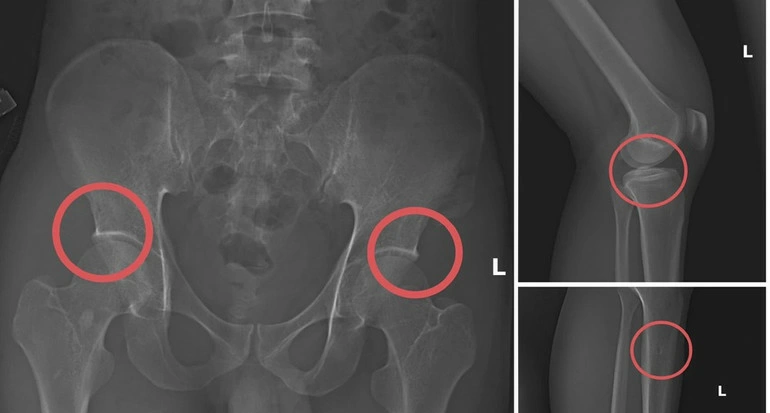

| Bản phim chụp XQ một số tổn thương xương do đối tượng tạo ra nhằm trục lợi tiền bảo hiểm nhân thọ. Ảnh: nhandan.vn |

Kết quả điều tra ban đầu của Công an tỉnh Phú Thọ cho thấy, đối tượng Tạ Minh Châu, nguyên nhân viên y tế, đã lợi dụng kiến thức chuyên môn để tổ chức gây thương tích giả, qua đó trục lợi hơn 6 tỷ đồng từ nhiều doanh nghiệp bảo hiểm nhân thọ.

Hoạt động diễn ra bài bản, có sự chuẩn bị kỹ lưỡng, sử dụng thuốc mê và dụng cụ tác động lực vào xương khớp người tham gia, phản ánh sự coi thường sức khỏe và phẩm giá con người ở mức đáng báo động.

Hậu quả trực tiếp chính là những tổn thương sức khỏe không thể đảo ngược. Việc chủ động đục vỡ xương khớp để tạo thương tích là hành vi cực kỳ nguy hiểm, dễ dẫn đến nhiễm trùng, tàn phế, suy giảm miễn dịch hoặc thậm chí tử vong khi xảy ra tai biến thuốc mê.